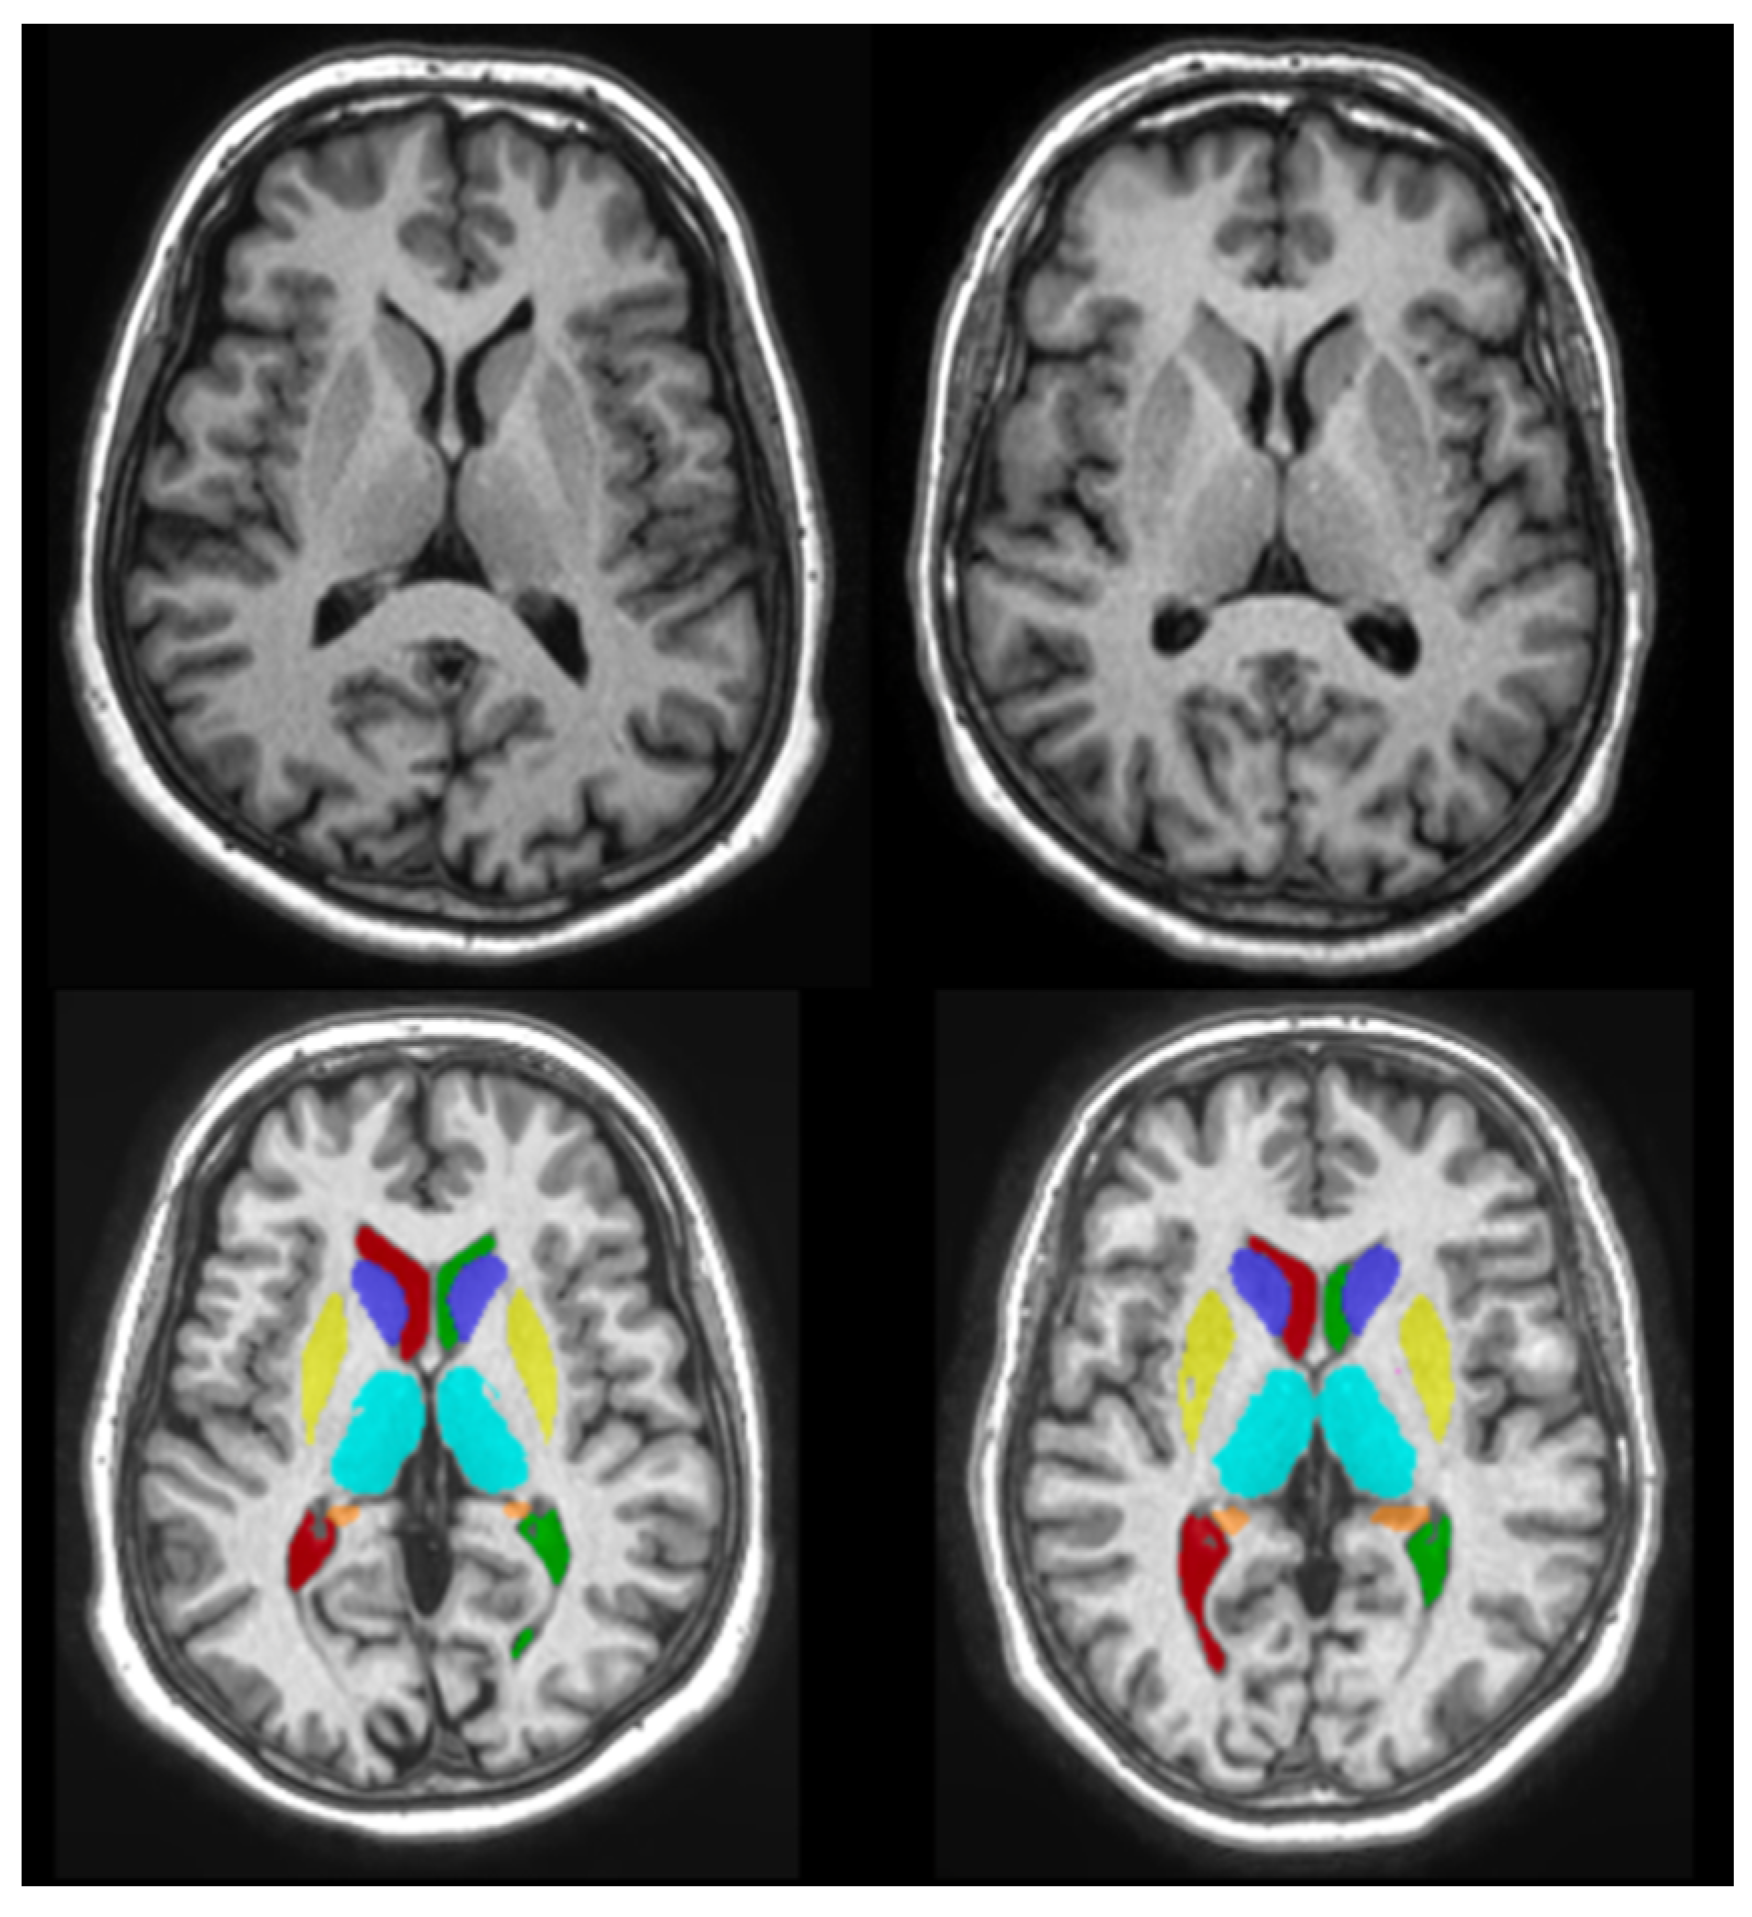

2.3.2. Volumetric Measurement Using volBrain